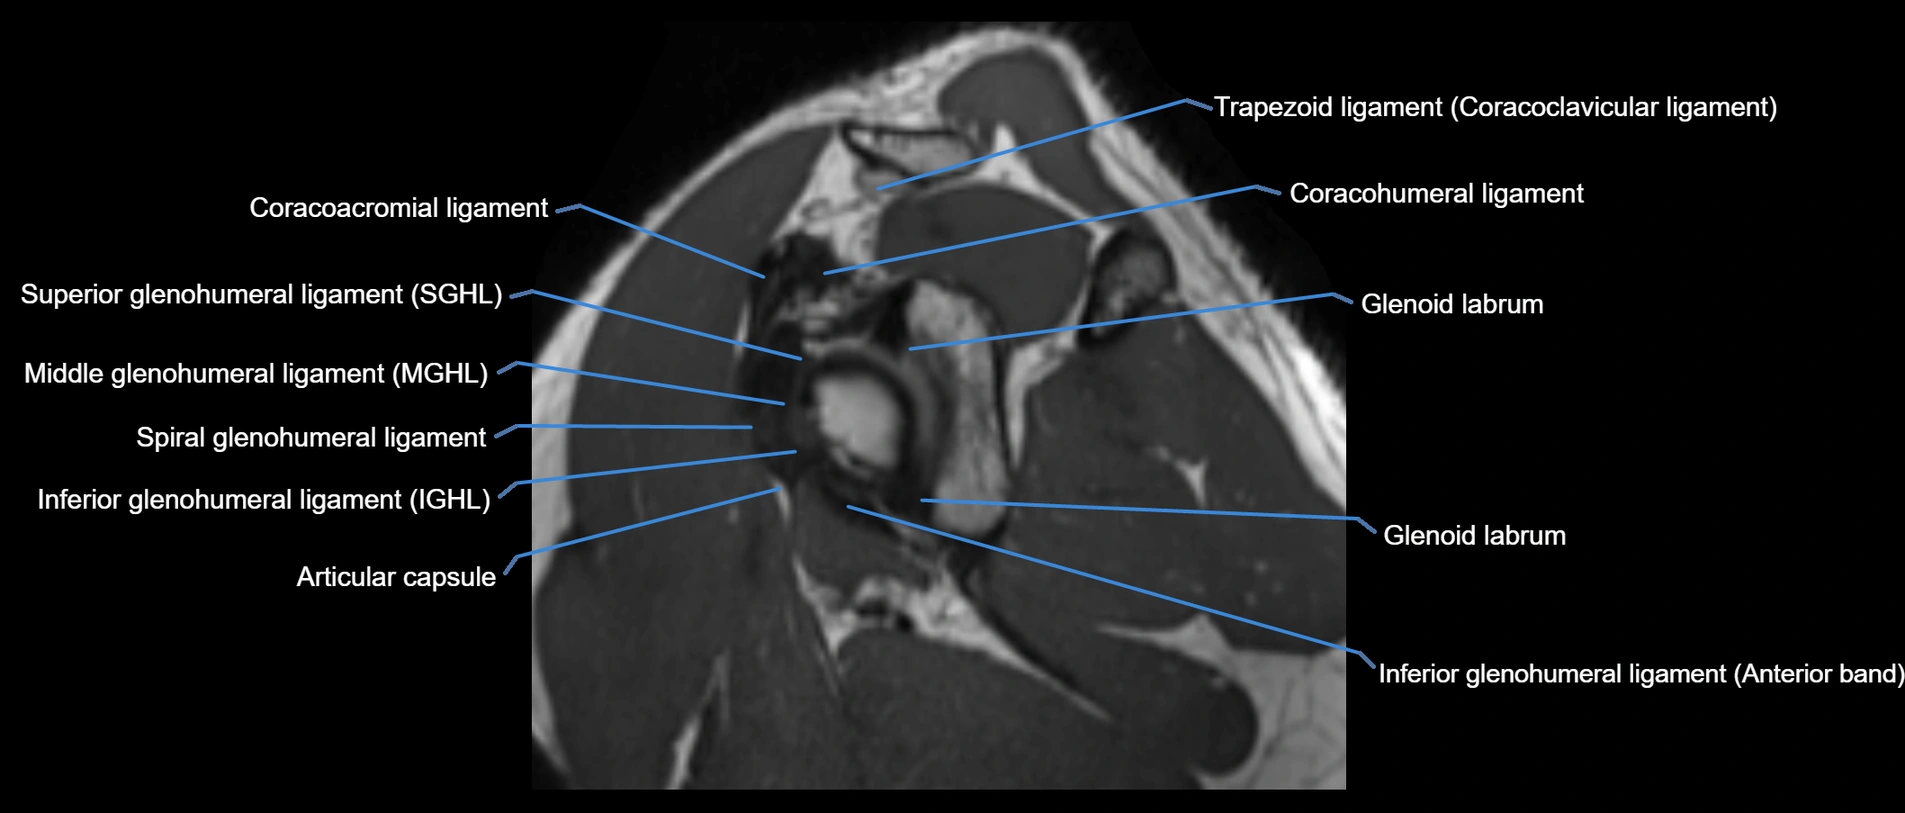

MRI images

image